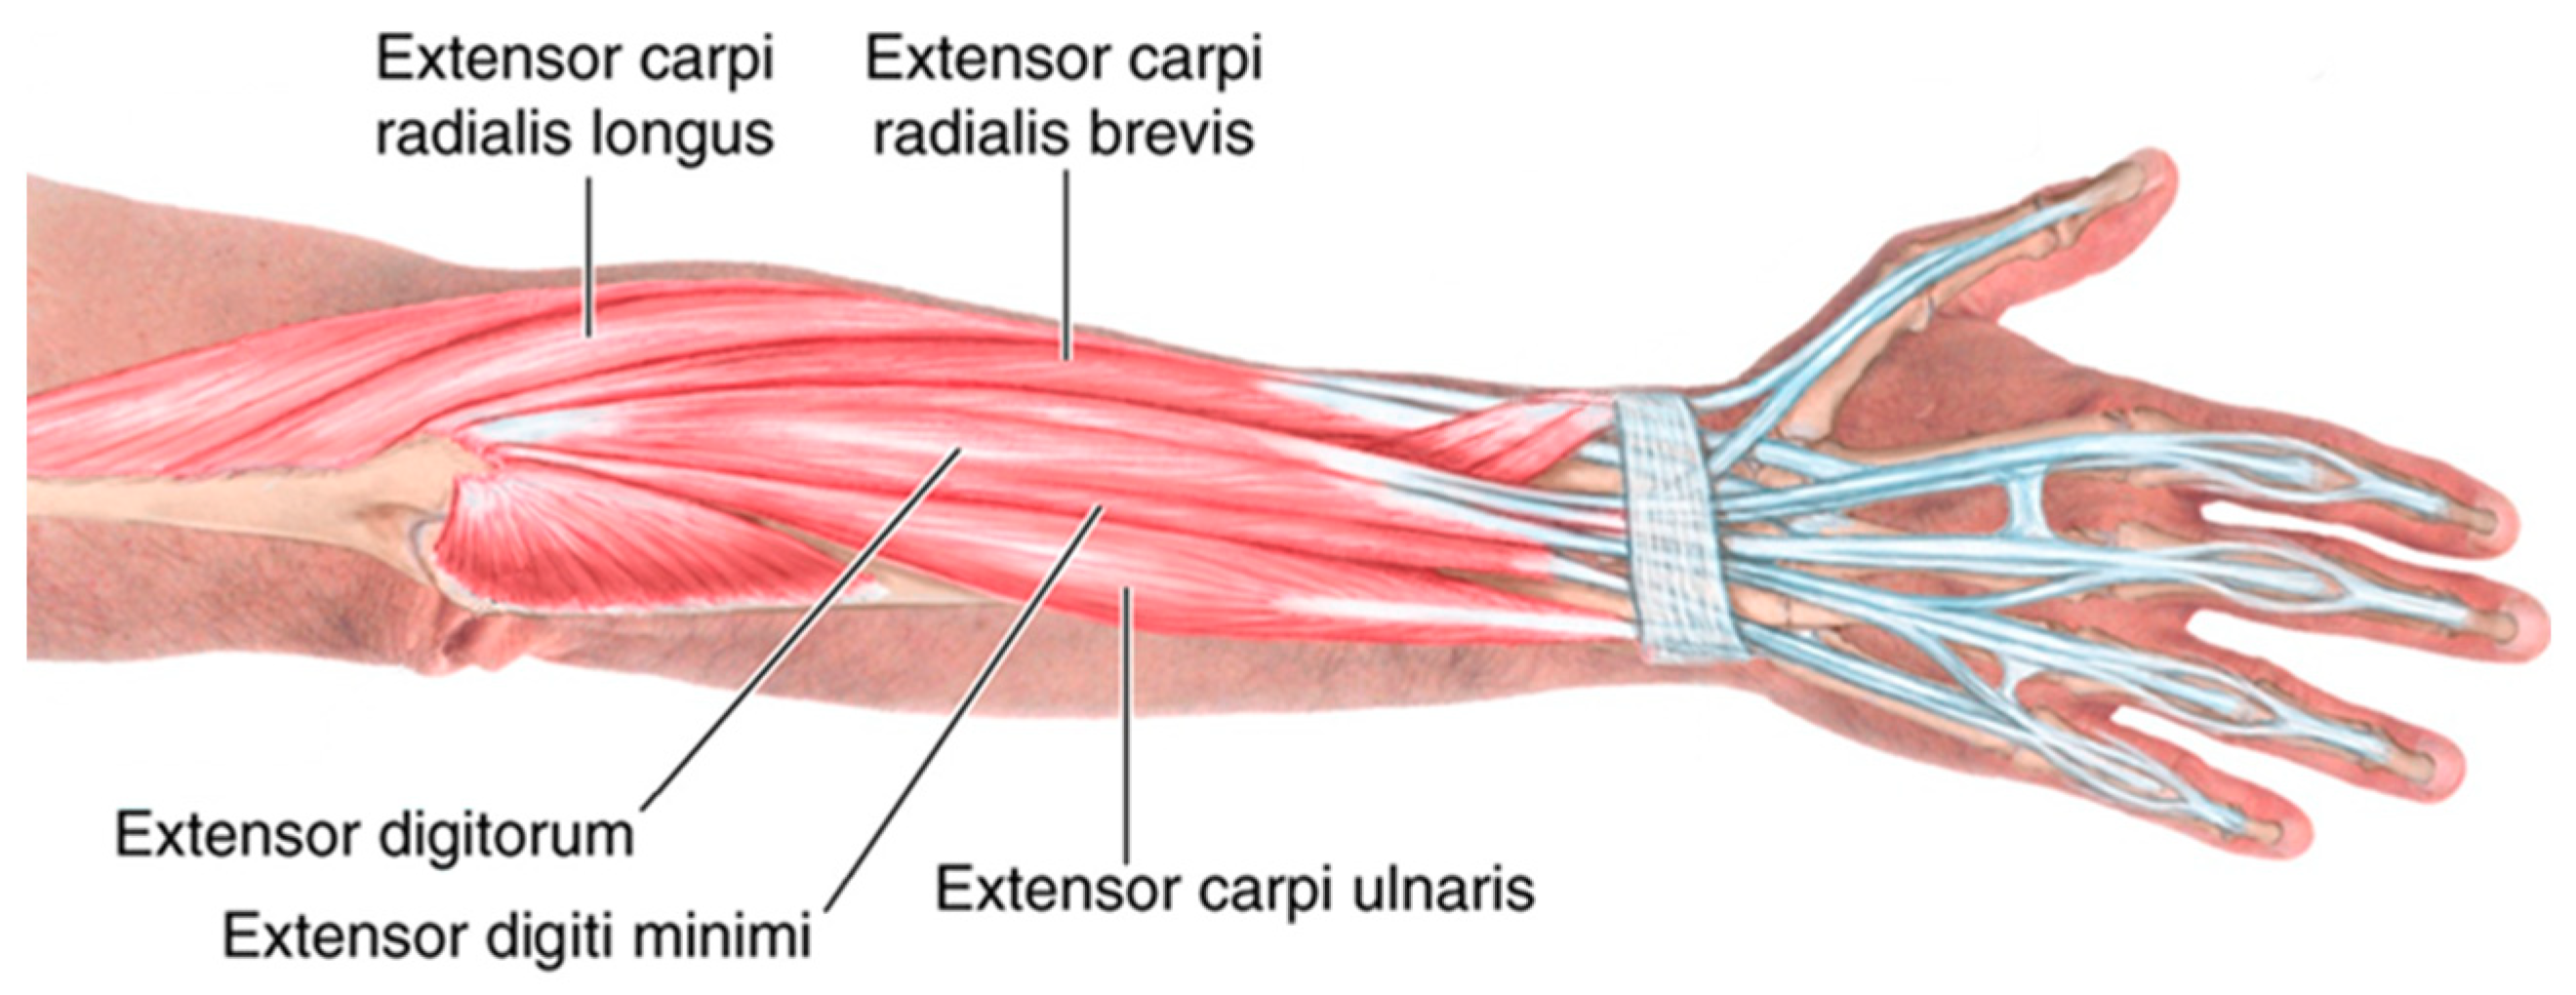

Анатомия и функции мышцы brachioradialis